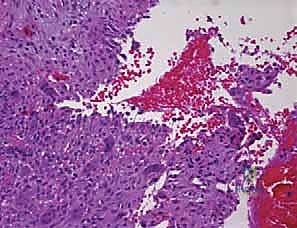

* التكوين النسيجي: لا يحتوي على سائل صافٍ، بل يحتوي على مساحات كيسية متعددة مملوءة بالدم. من الناحية المجهرية، هذه المساحات ليست أوعية دموية حقيقية (تفتقر للبطانة الوعائية)، بل تفصلها حواجز ليفية تحتوي على خلايا عملاقة (Giant Cells) وعظم غير ناضج. هذا التمييز النسيجي حاسم لفهم سبب نزيفها الشديد أثناء الجراحة وطبيعتها العدوانية.

صورة مجهرية توضح الفحص النسيجي لكيس العظم المتمدد (ABC)، حيث تظهر الحواجز الليفية والخلايا العملاقة التي تحيط بالمساحات المليئة بالدم، وهو ما يفسر السلوك العدواني الموضعي لهذا النوع من الأكياس.